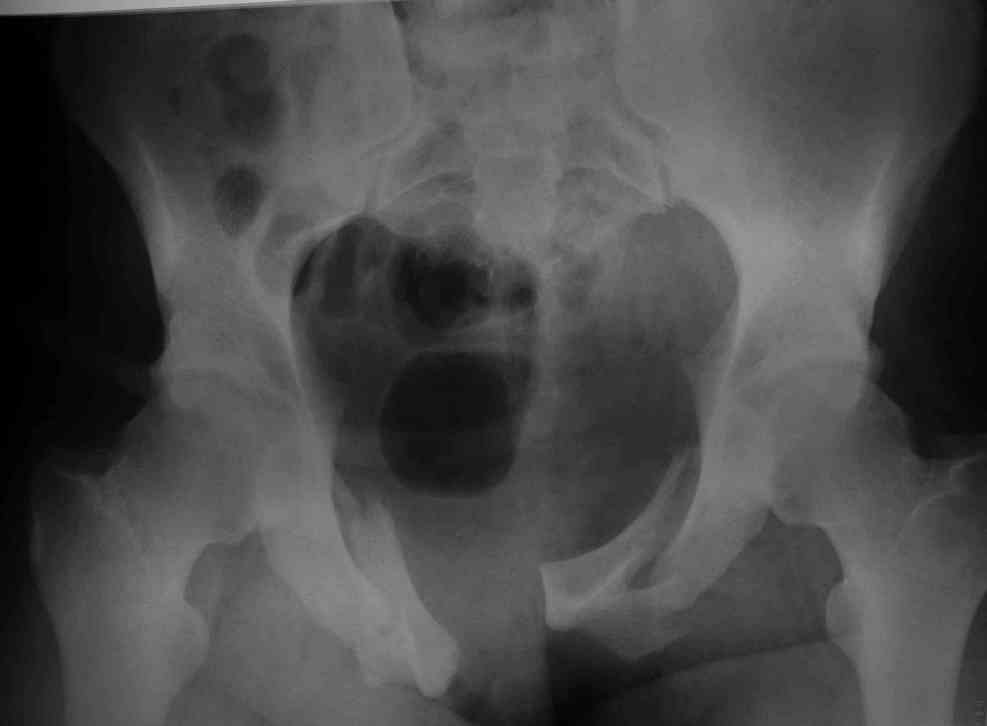

Уважаемые коллеги! опять вопрос по повреждению таза. Больной получил производственную травму 10 дней назад - удар балкой около 3 тонн в область верхней трети правого бедра и лона.

Был диагностирован перелом "типа бабочки" и повреждение уретры. Сделана цистостома. У нас в отделении 3 дня. Имеется огромная флюктуирующая гематома с "галифе"-образной деформацией обеих бедер. Пнкционно эвакуировали в несколько приемов из подфасциальных полостей на бедрах около 3 литров геморрагического отделяемого с последующей эластической компрессией. При пункциях выявлено сообщение полостей на бедрах - видимо через поравннуюдиафрагму дна и полость таза - при удалении крови справа уменьшался объем левого бедра. Какой то активности проявялять пока боимся - аппаратная фиксация через отслоенные ткани представляется чреватой нагноением, открытая фиксация в условиях такой гематомы тоже не радует. Хотелось бы услышать ваше мнение